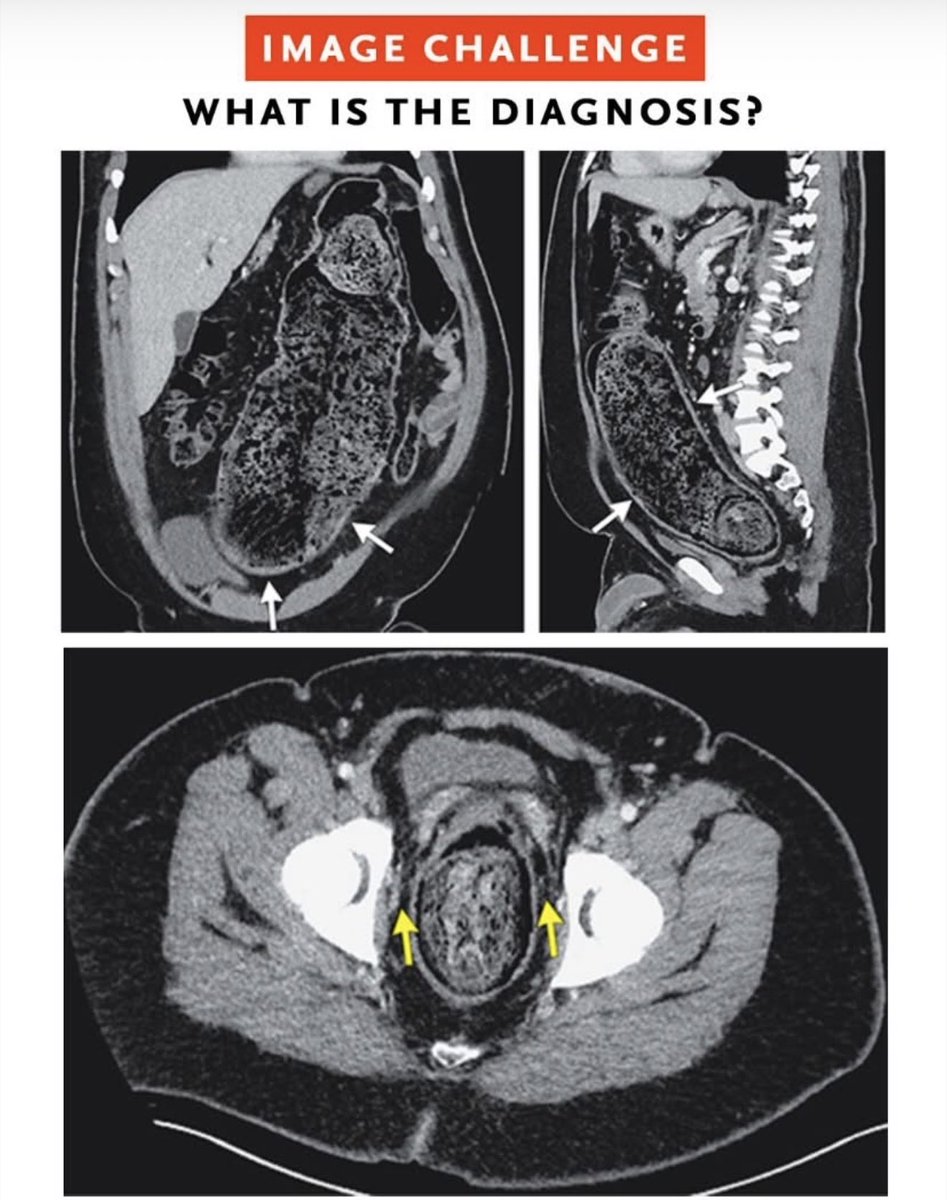

Chirurg in Tilburg. Colorectal surgeon, certified coloproctologist. Surgical Oncologist. Laparoscopic and transanal surgery. Robotic surgery. #colorectalsurgery